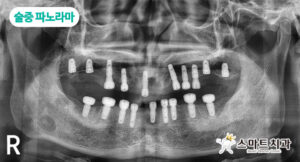

환자분께선 장사를 하시다 보니 여러 번 내원이 어려워 하루에 전악 발치 후 식립 (18개)을 원하시고 임시 틀니도 당일 장착 원하셔서 발치 전 미리 제작해 드렸습니다.

식립 위치와 힐링 어벗 연결 등으로 잘 맞지 않아서 재제작 가능성을 고지했으나 비용이 더 들더라도 당일 제작을 원하셔서 임시 틀니 제작 후 식립을 진행했으며, 상악 좌측 부위는 골질이 좋지 않아 제2소구치 위치에 예비용으로 하나 더 식립하여 총 상악 10개, 하악 9개 임플란트 식립하였습니다.

수술 후 임시틀니를 넣어 드렸지만, 힐링 어벗 등으로 잘 맞지 않아 술후 재인상하여 임시 틀니 재제작을 해드렸습니다.